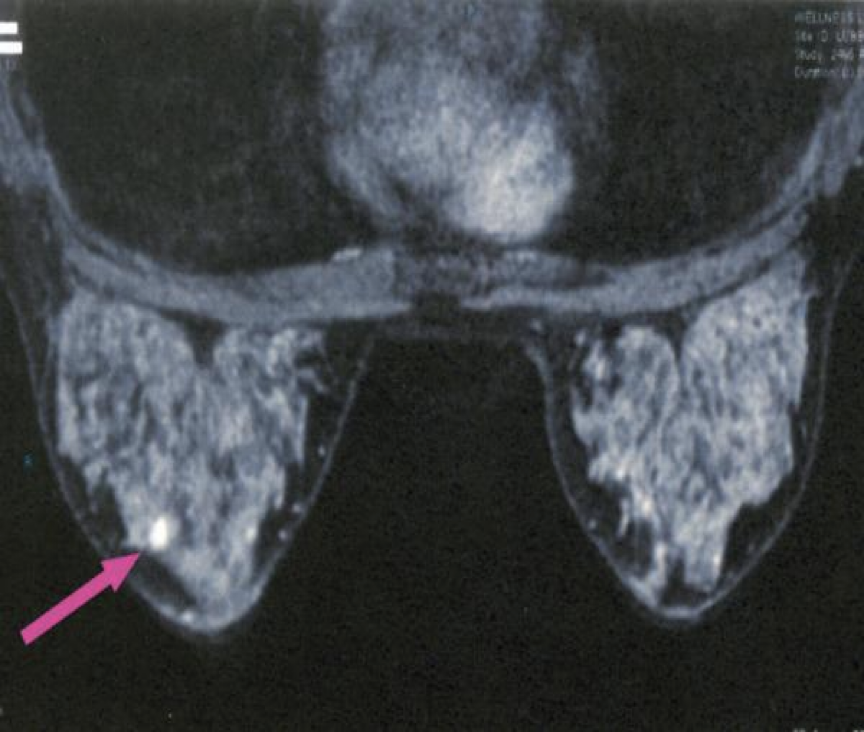

MRI: Superior modality to:Â lymph node examination leading to no results from other modalities, except MRI